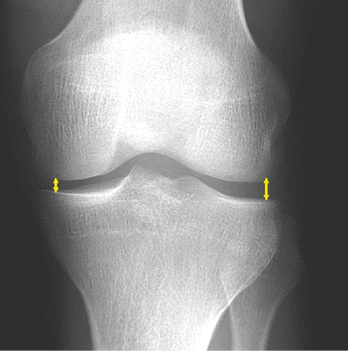

Sonderfall „definitive“ Gelenkspaltverschmälerung ohne Osteophyten

Die Kellgren-Lawrence-Skala wird seit jeher kontrovers diskutiert, da sie einen starken Fokus auf osteophytäre Anbauten legt. Dadurch wird die atrophe Form der Arthrose (  Abb. 6 ), bei der es zur Gelenkspaltverschmälerung ohne wesentliche Osteophyten kommt, vernachlässig und kann nicht klar eingestuft werden. Hierfür schlägt die Konsensusarbeitsgruppe BK 2112 (2014) vor, dass diese analog zu Kellgren-Lawrence-Grad 3 oder 4, Letztere wenn eine starke Verschmälerung und definitive Verformungen des Femurs und der Tibia vorliegen, einzustufen.